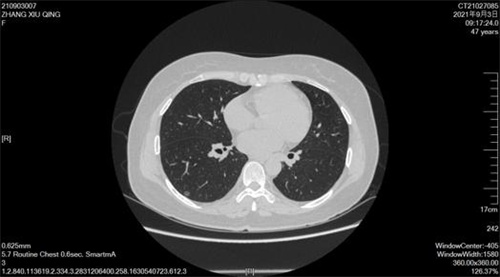

近日,我院胸心外科团队协同麻醉团队再次完成了非气管插管麻醉下电视胸腔镜右肺下叶楔形切除术,该例患者是我院开展的第一例艾滋病合并肺癌无管微创手术。 张某确诊艾滋病已有...